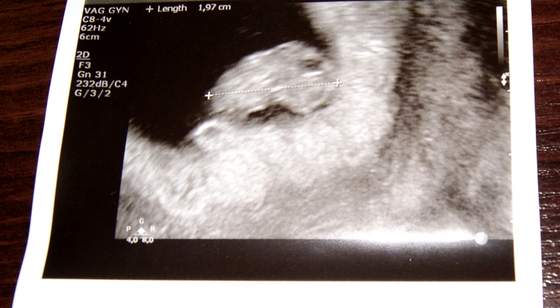

to zdjęcie z usg moje z wczoraj

Zobacz załącznik 524283

Justyna, Mgielka piękne maluszki

Zapomniałam napisać, że mój Okruszek ma 3,7cm. I termin wg USG się idealnie pokrył z terminem wg ostatniej @.